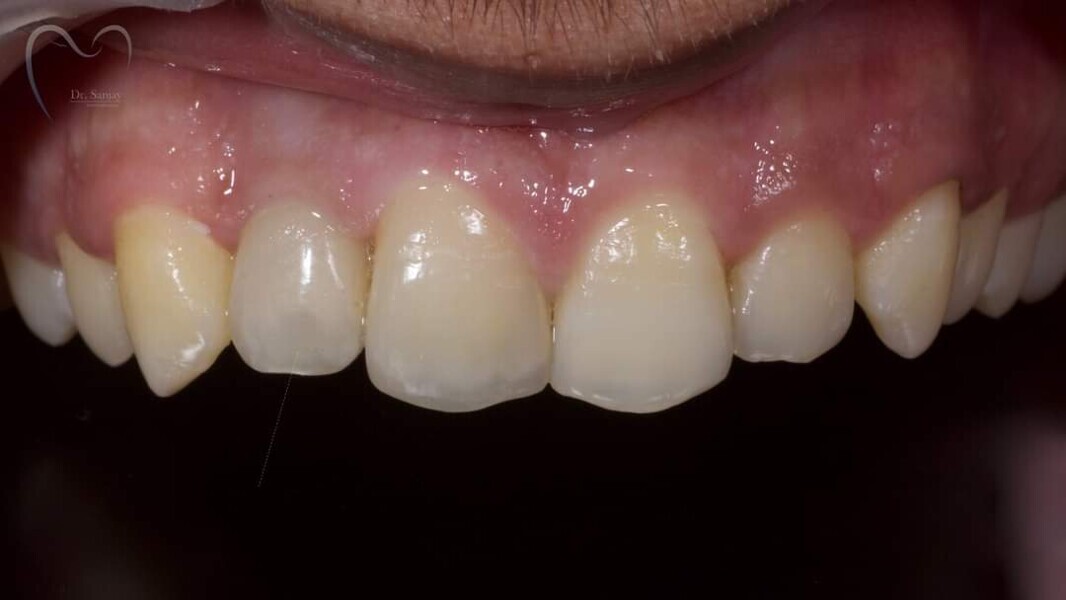

Esthetic Rehabilitation of Maxillary Anterior Teeth: Dr Sanjay Sah